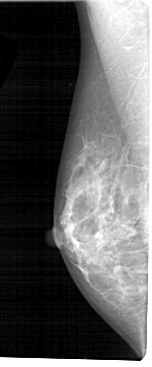

A_1497_1.LEFT_MLO

LEFT_MLO LINES 5491 PIXELS_PER_LINE 2266 BITS_PER_PIXEL 12 RESOLUTION 43.5 NON_OVERLAY